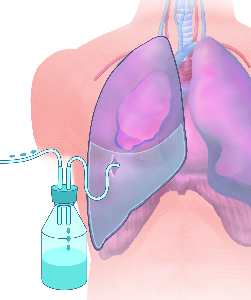

Detailreiche Fotografien aus der medizinischen Praxis ergänzen die Texte; moderne, genaue,

wissenschaftliche Zeichnungen geben Einblick in die Anatomie und die Funktion der Lunge und

anderer Organe.